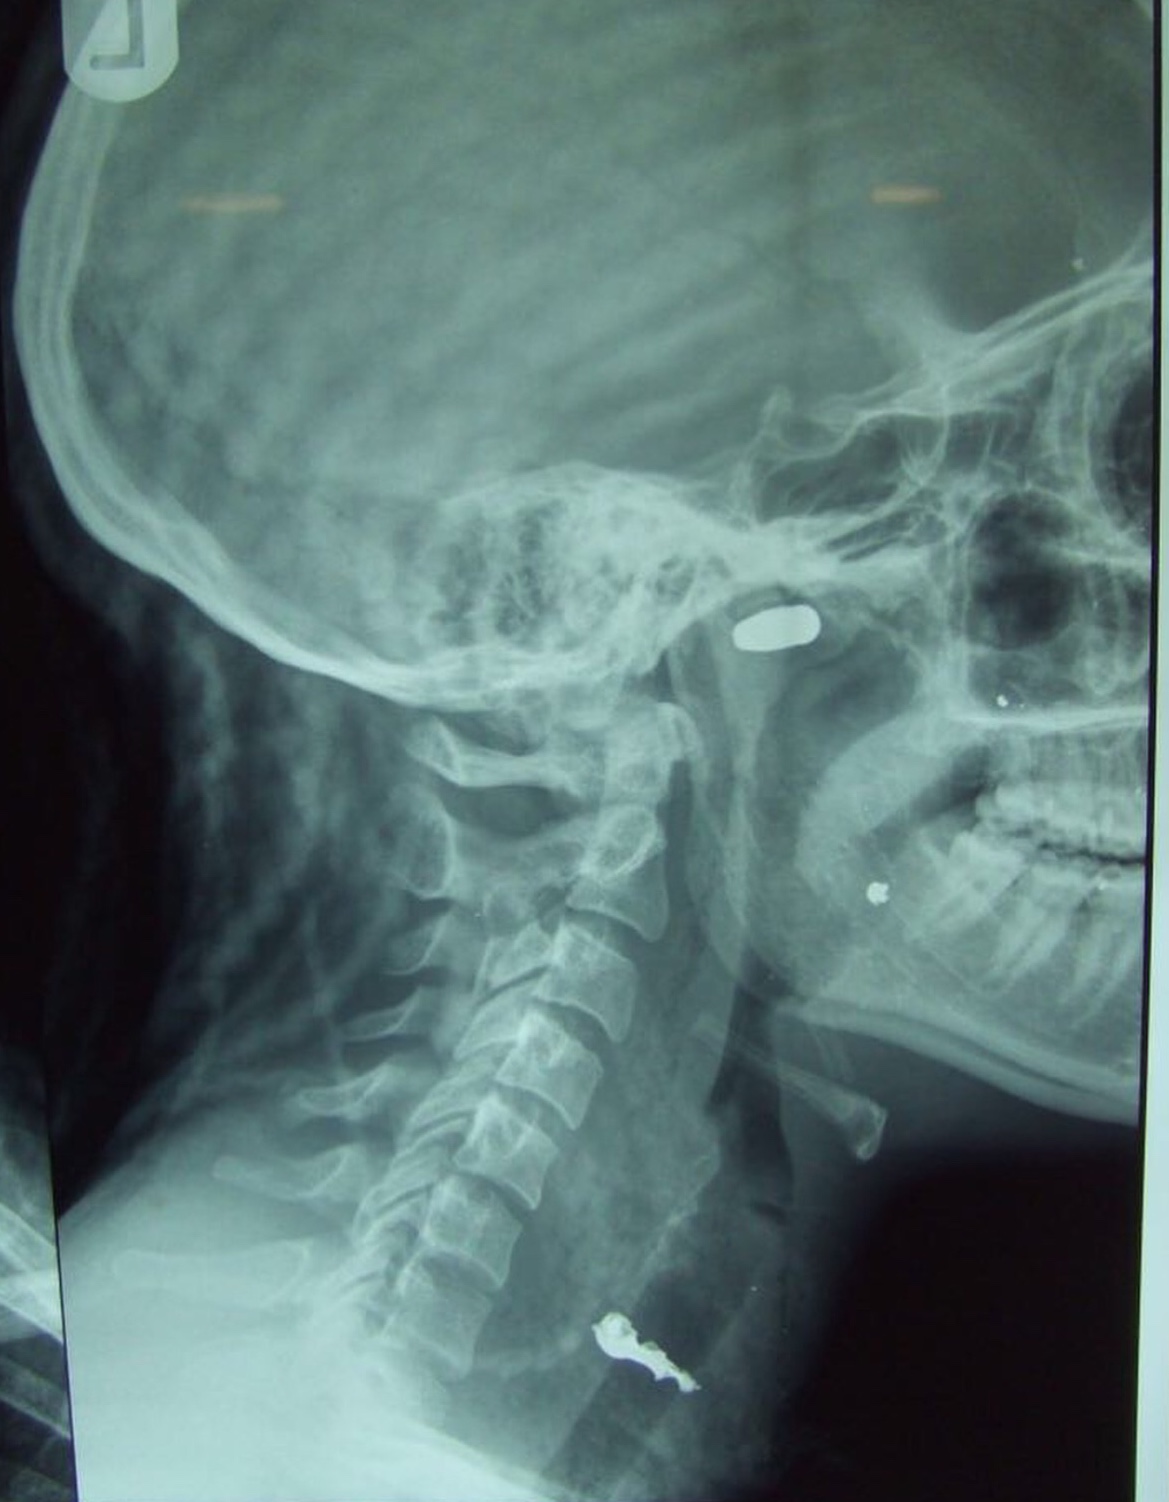

Nigerian artiste and nudist Maheeda celebrates her birthday today. She took to social media to recounts how she was prayed for by a girl, after she was shot by armed robbers. Read what she wrote and the pictures she shared below: